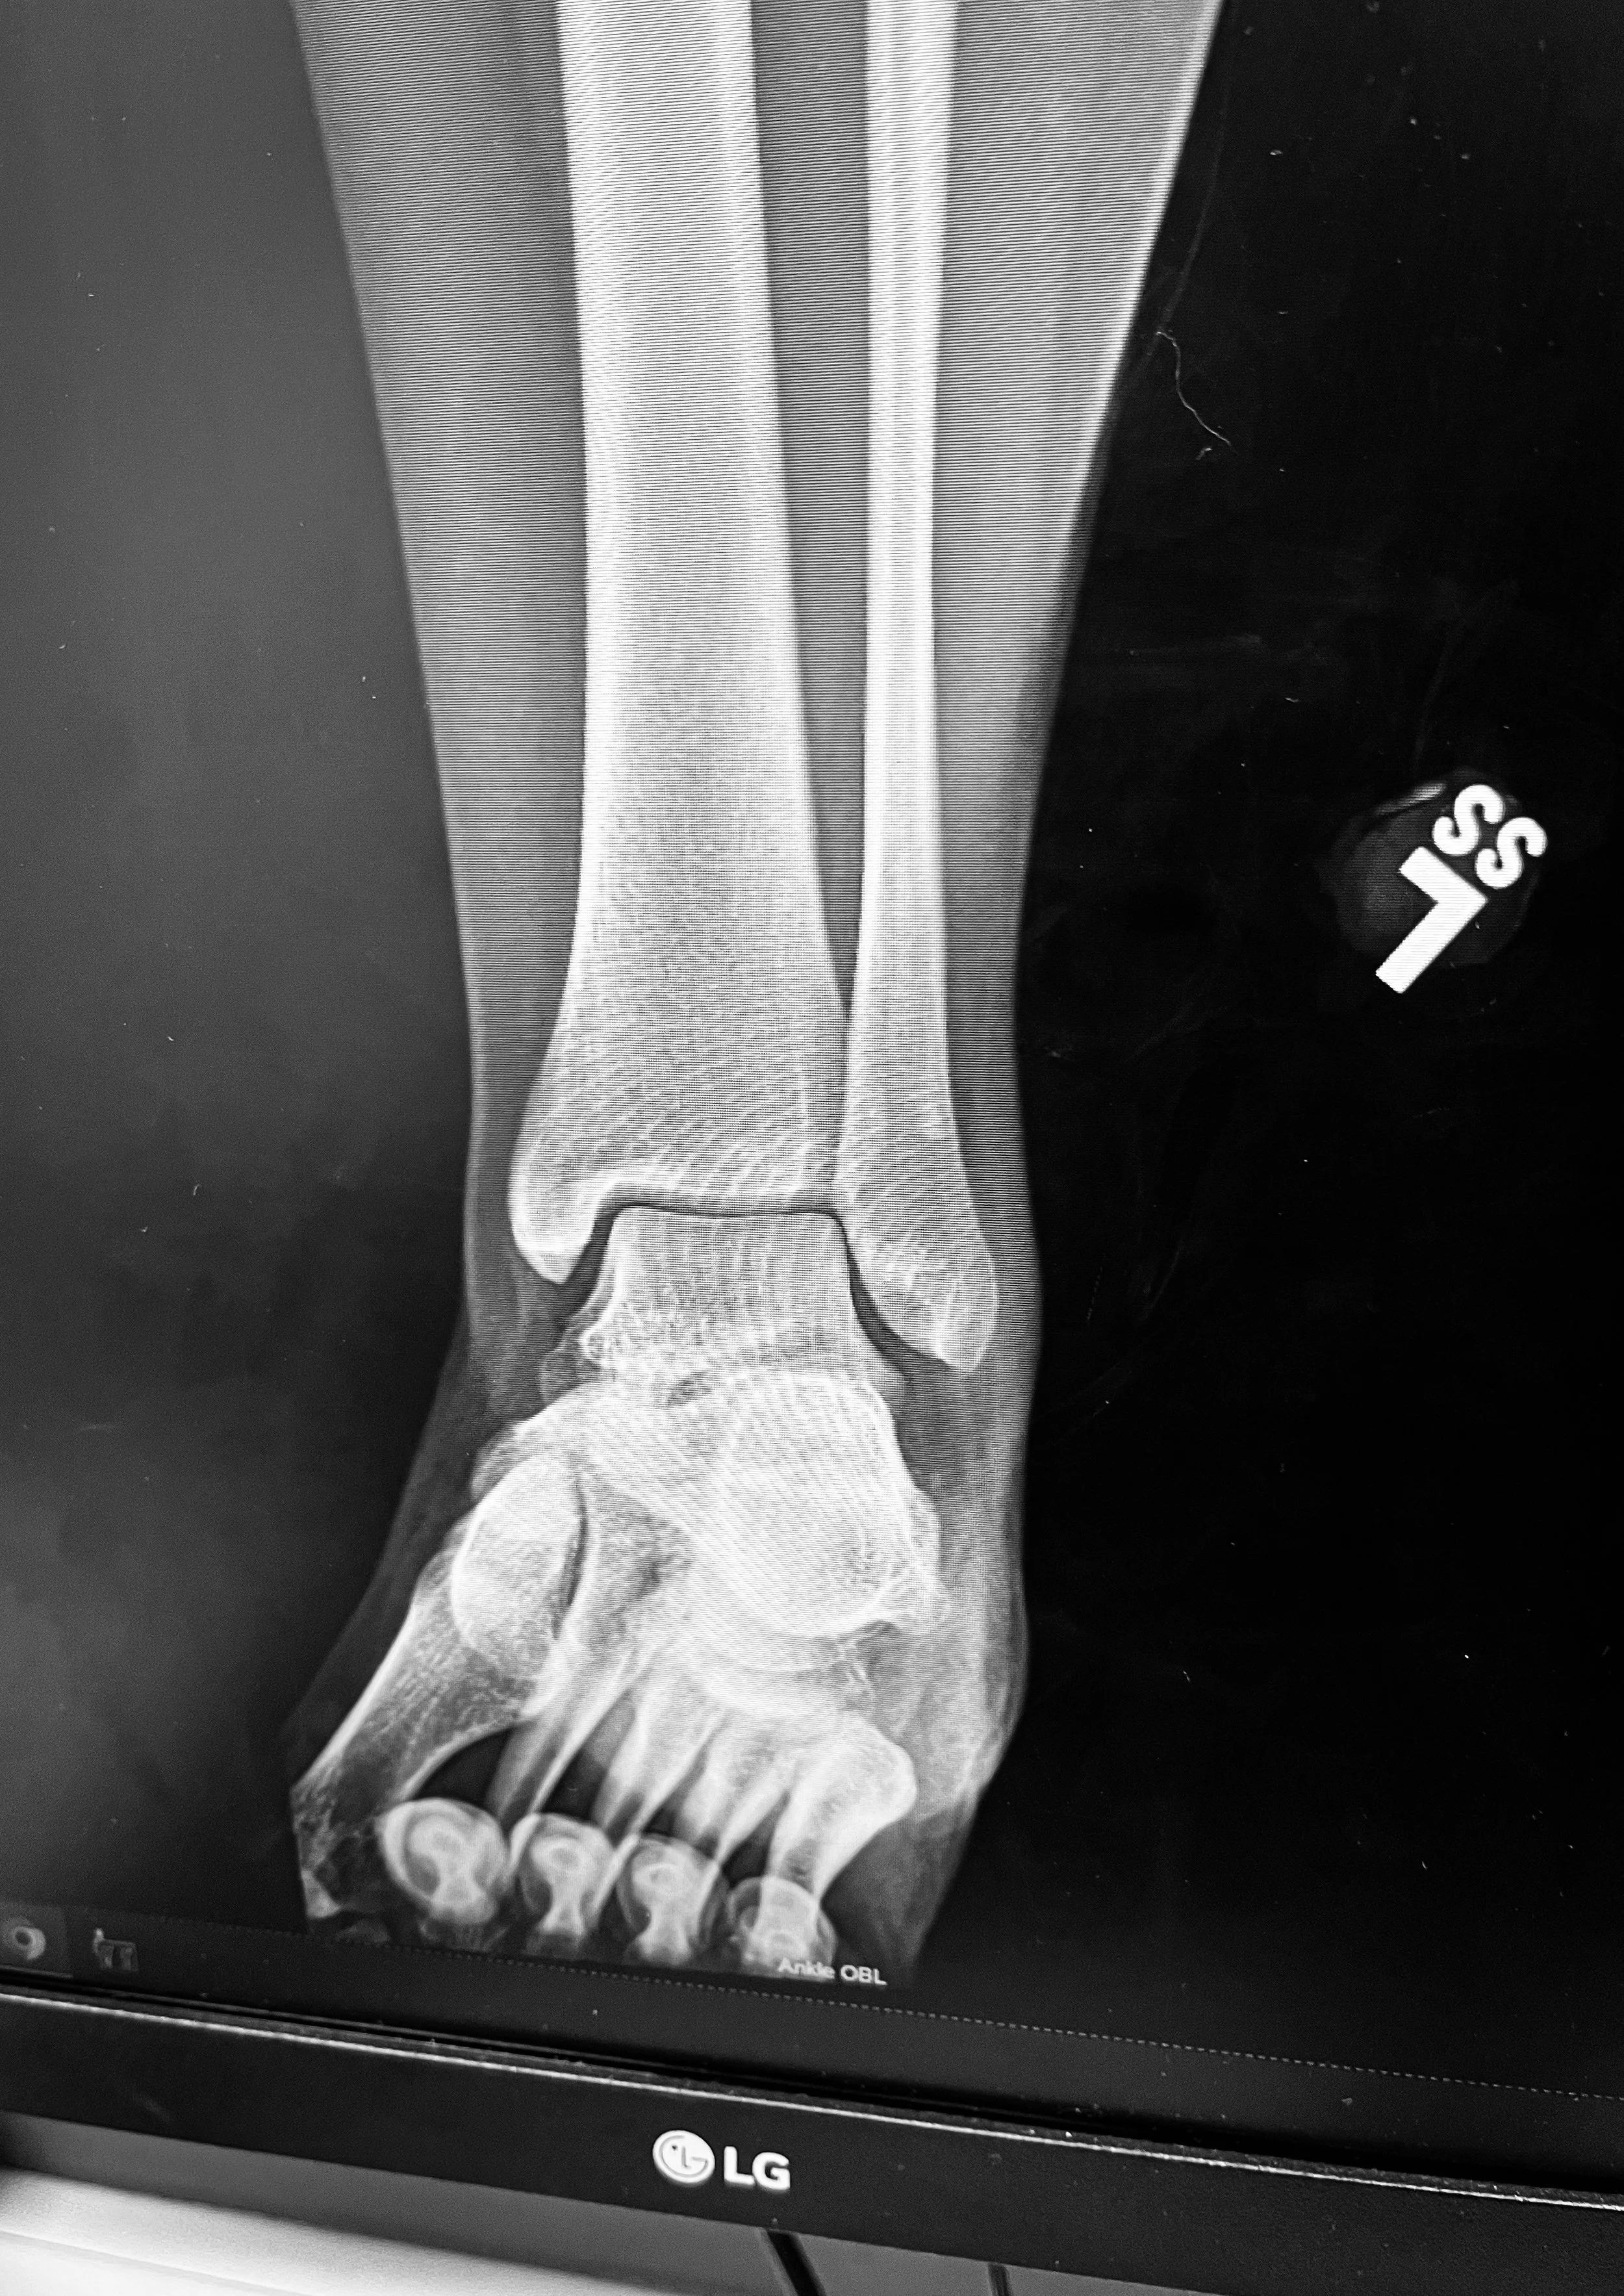

Twenty Twenty-Five did not start off the way I wanted it to, just before Christmas, I fell and bruised my ankle bone so I was in a walking boot. I had just lost my paint horse Gypsy, completely unexpectedly, my lifelong dachshund Harley in October, my Nana in July, and my 5 year old bloodhound and German shepherd mix, Scout to cancer in May.

To say I started off 2025 on the wrong foot was an understatement. I was grieving, and told to stay off my ankle. (Which I honestly didn’t do that well of) but the whole year was bad, sure the grief is still there, I took that same grief into 2026. But there was a lot of good too. I can confidently say I’m not the same person I was on Jan 1, 2025.